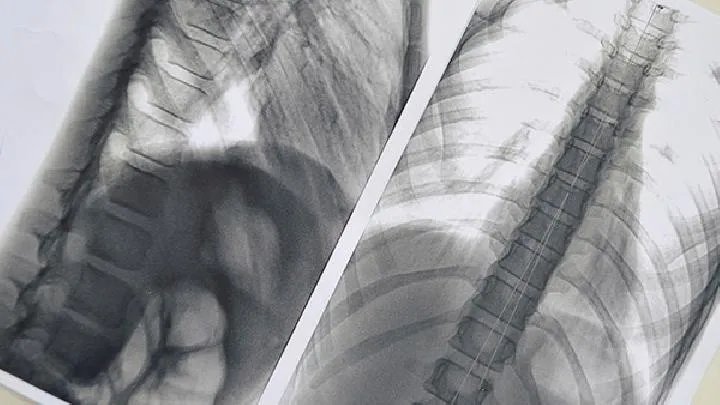

小细胞肺癌病人还会出现某个肺叶、肺段反复发生肺炎;肺结核病人抗痨治疗无效,X线见肺内阴影继续增大等等,均需警惕小细胞肺癌的发生,需作进一步检查。